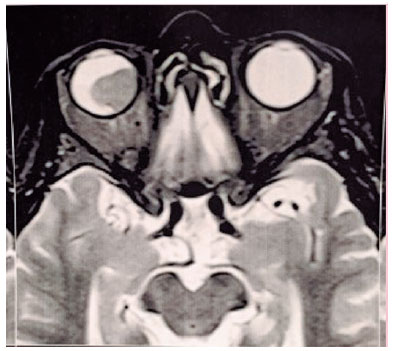

An 85-year-old Caucasian woman was referred in March 2017 for consultation after a fine-needle biopsy in an elevated choroidal tumor in the right eye (OD), by an outside ophthalmologist. The lesion was diagnosed following a complaint of 2-month unilateral progressive vision loss. Ocular magnetic resonance imaging and ultrasonography before the procedure demonstrated a single choroidal mass with associated serous retinal detachment (Figures 1 and 2), and fluorescein angiography showed a nasal choroidal mass (Figure 3).